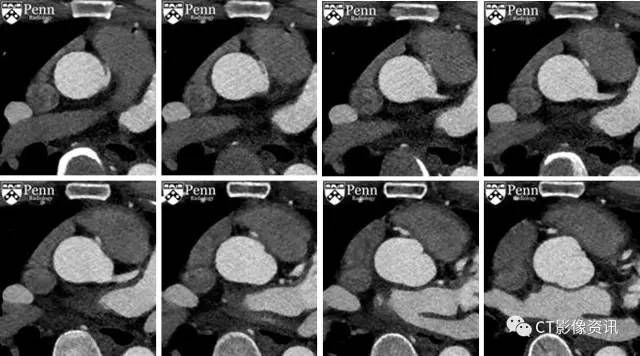

门控冠脉CTA成像,轴位图像

复习轴位图像